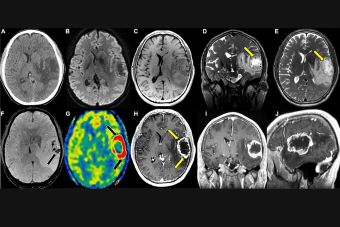

Diagnosis of Hodgkin lymphoma typically involves a combination of physical examination, imaging studies (such as CT scans and PET scans), and biopsy of lymph nodes or affected tissues. Dr. Shweta Bansal utilizes these diagnostic tools to confirm the presence of Hodgkin lymphoma and determine the most appropriate treatment approach.